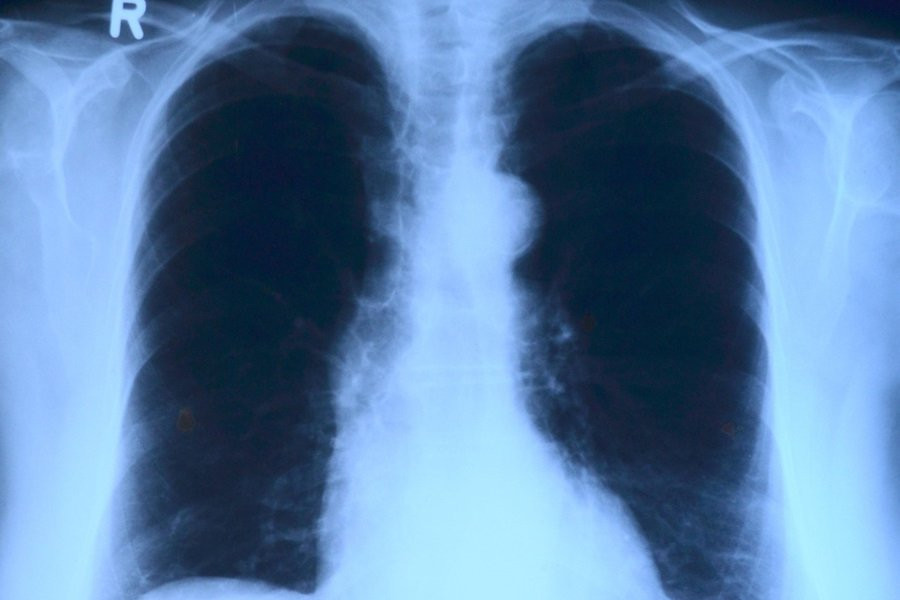

Фото из открытых источников

Искусственный интеллект теперь способен определить возраст человека, анализируя рентгеновские снимки грудной клетки. Эту новость сообщает журнал The Lancet.

Исследователи из Высшей школы медицины Осаки (Япония) протестировали модель искусственного интеллекта на 67 099 рентгенограммах грудной клетки. Эти снимки были сделаны в период с 2008 по 2021 год и принадлежали 36 051 здоровому человеку. Модель искусственного интеллекта успешно определила связь между предполагаемым возрастом, вычисленным на основе анализа ИИ, и реальным хронологическим возрастом людей. Коэффициент корреляции составил 0,95, что свидетельствует об очень сильной связи между этими показателями. Дополнительно эксперты использовали 34 197 рентгенограмм грудной клетки от пациентов, у которых уже были диагностированы различные заболевания.

Исследование показало, что разница между возрастом, определенным искусственным интеллектом, и хронологическим возрастом пациента была связана с определенными заболеваниями. Вероятность наличия гипертонии, гиперурикемии и хронической обструктивной болезни легких увеличивалась с ростом предсказанного возраста, полученного ИИ.